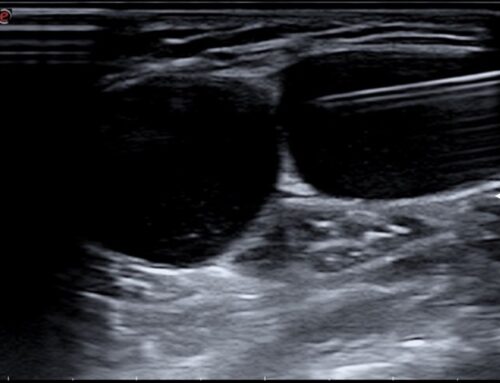

- Técnica. El corticoide debe inyectarse dentro de la vaina tendinosa y nunca dentro del tendón. Para asegurar el éxito de la técnica, la infiltración debe realizarse con guía ecográfica continua.

Consiste en cortar o seccionar la polea que impide el paso del tendón. Se trata de una técnica mínimamente invasiva que se realiza con aguja, cuyo bisel hace la función de un bisturí y con visualización continua mediante ecografía se realiza una sección de la polea, pudiendo liberar así al tendón atrapado.